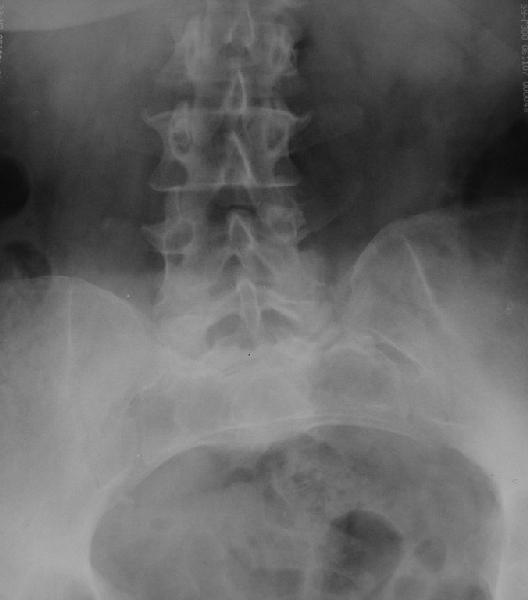

У больной 53 лет в последний год появились сильные боли в пояснице.

Пациентку в первую очередь беспокоят боли в спине, на отсутствие

движений в суставе она вроде и не жалуется. Вопрос насчет тактики.